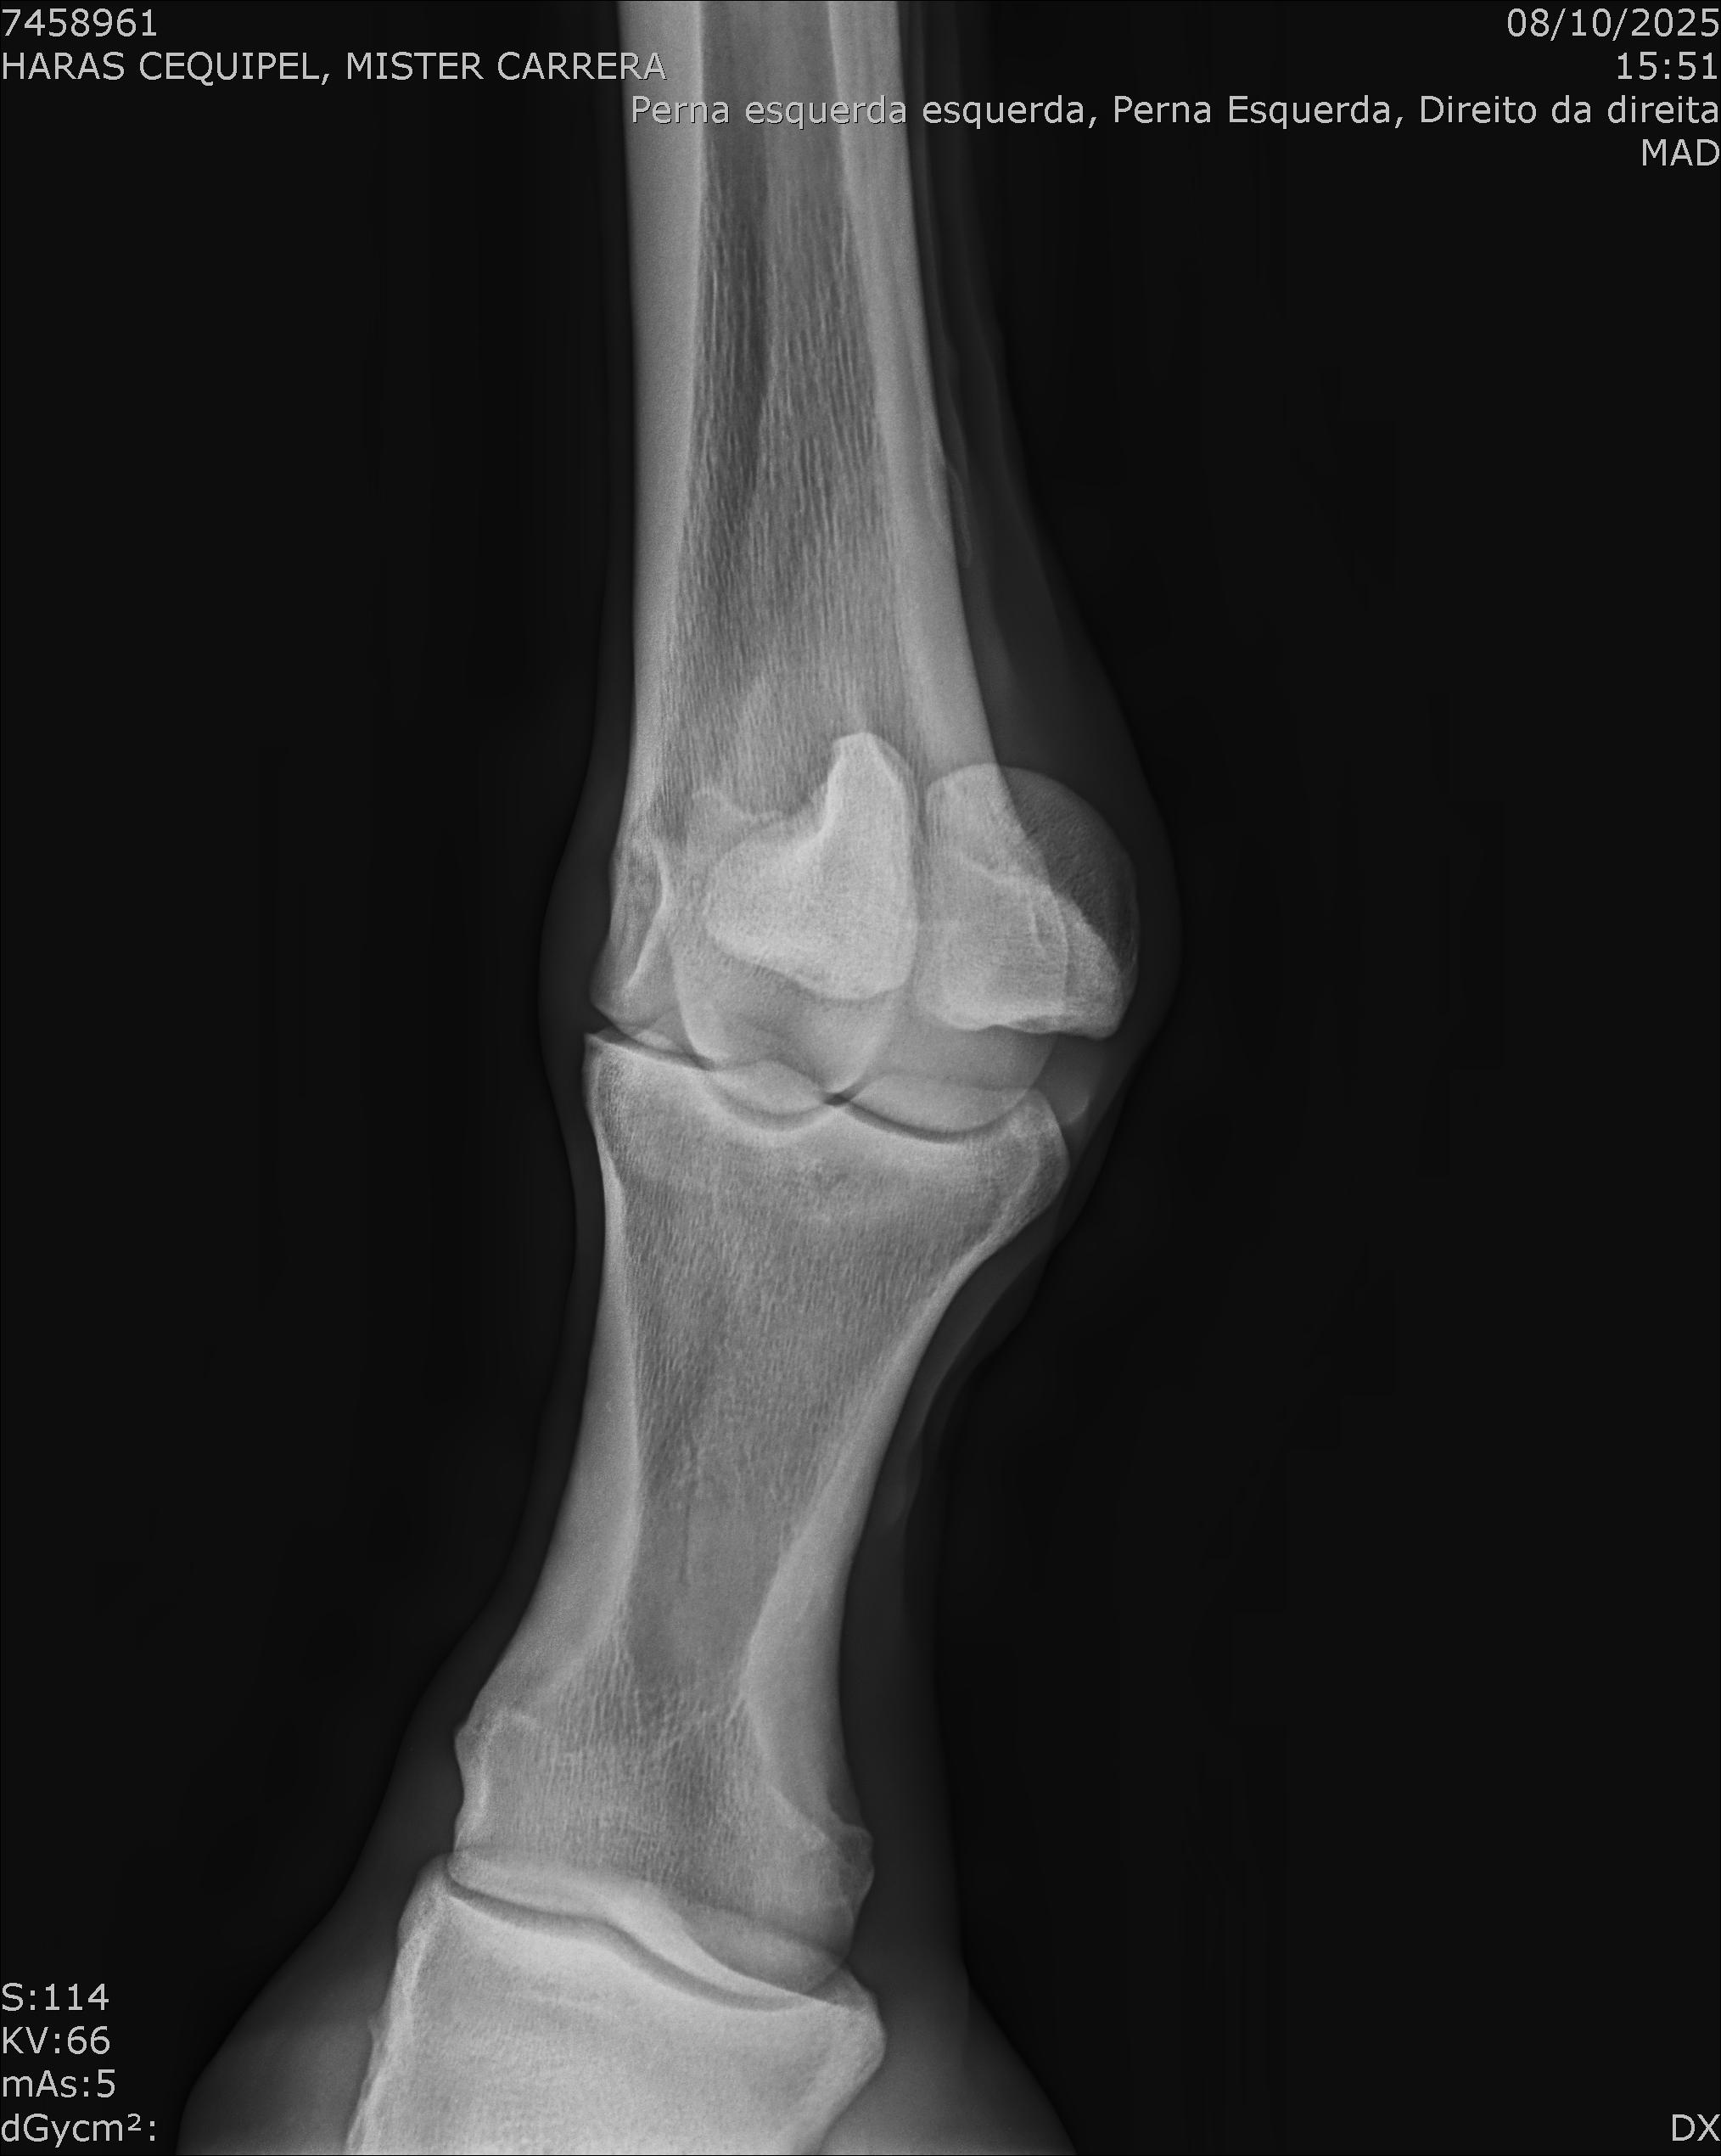

:: RAIOS-X DO LOTE